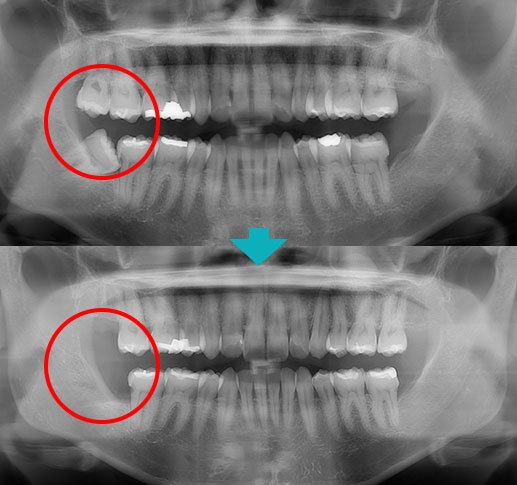

before

after

| ■性別・年代 | 女性・40代 |

|---|---|

| ■治療内容 | 汚れが溜まり虫歯があり右下の親知らずを抜歯しました。 |

| ■金額 | 埋伏抜歯 5,120円 CT 4,400円 |

| ■治療期間 | 1日 |

| ■通院回数 | 1回 |

| ■リスク・副作用 | 抜歯後にしびれが出ることや、まれに腫れや痛みが長引くことがあります。 |